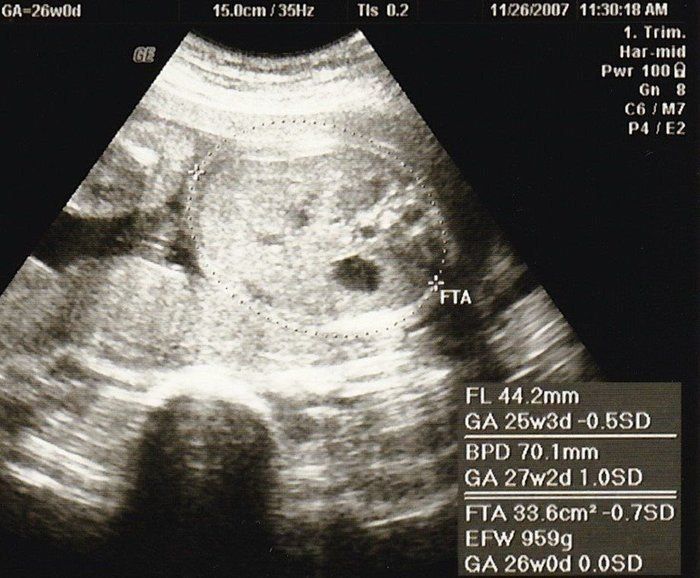

宮本真知さんの妊娠26週目のエコー写真

妊娠中期検査ということで再び血液検査をしました。今回はHTLV-1(ヒトT細胞白血病ウイルス)とクラミジア抗体のチェックです。さらに血糖検査で、気の抜けたサイダーみたいなブドウ糖液を飲み、60分後の血糖値を測りました。赤ちゃんは前回と同じく、BPD、AC、FLを測ってもらい発育をチェック。赤ちゃんの推定体重は804g。3Dエコーでは、こっちを向いて笑っている(?)表情が見られました。